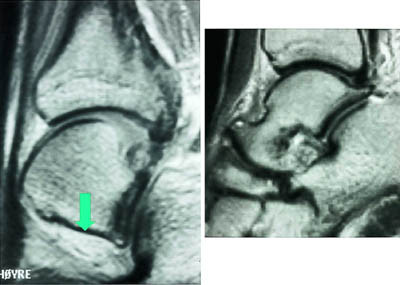

Mesteparten av sinus tarsi er fylt med fett. Dette gir høysignal på T1-vektet sekvensog lavsignal på fettsuppresjonssekvenser. Blodkar og nervefibrer gir små punktformige lavsignaler medialt i fettvevet på T1-vektet sekvens. Ligamentene gir lavsignal på spinnekkosekvensene. Figur 1 viser en normal sinus tarsi. I koronalplanet sees ligamentum cervicale ventralt og ligamentum interosseus noe lenger dorsalt. Det mest fremtredende og hyppigste MR-funnet ved sinus tarsi-syndrom er lavsignalområder på T1-vektet sekvens og lav- eller høysignalområder på T2-vektet sekvens. Forandringene er forårsaket av fibrose (fig 2) med eller uten inflammasjon (fig 3). Av og til kan vi se små væskelokulamenter som representerer ganglioncyster (fig 4). Ligamentene kan være vanskelig å se, enten fordi det er mye inflammasjon eller fordi de er røket. Hos en del pasienter kan man finne ruptur av laterale ankelligamenter, spesielt ligamentum talofibulare anterior.

I tillegg til å kunne påvise patologiske forandringer i sinus tarsi kan vi påvise andre årsaker til smerter lateralt i bakfoten: Osteokondrale skader ved øvre laterale talushjørne, avaskulære nekroser og stressfrakturer i omliggende knokler samt patologi i omliggende ligamenter og sener (fig 5) og (fig 6).